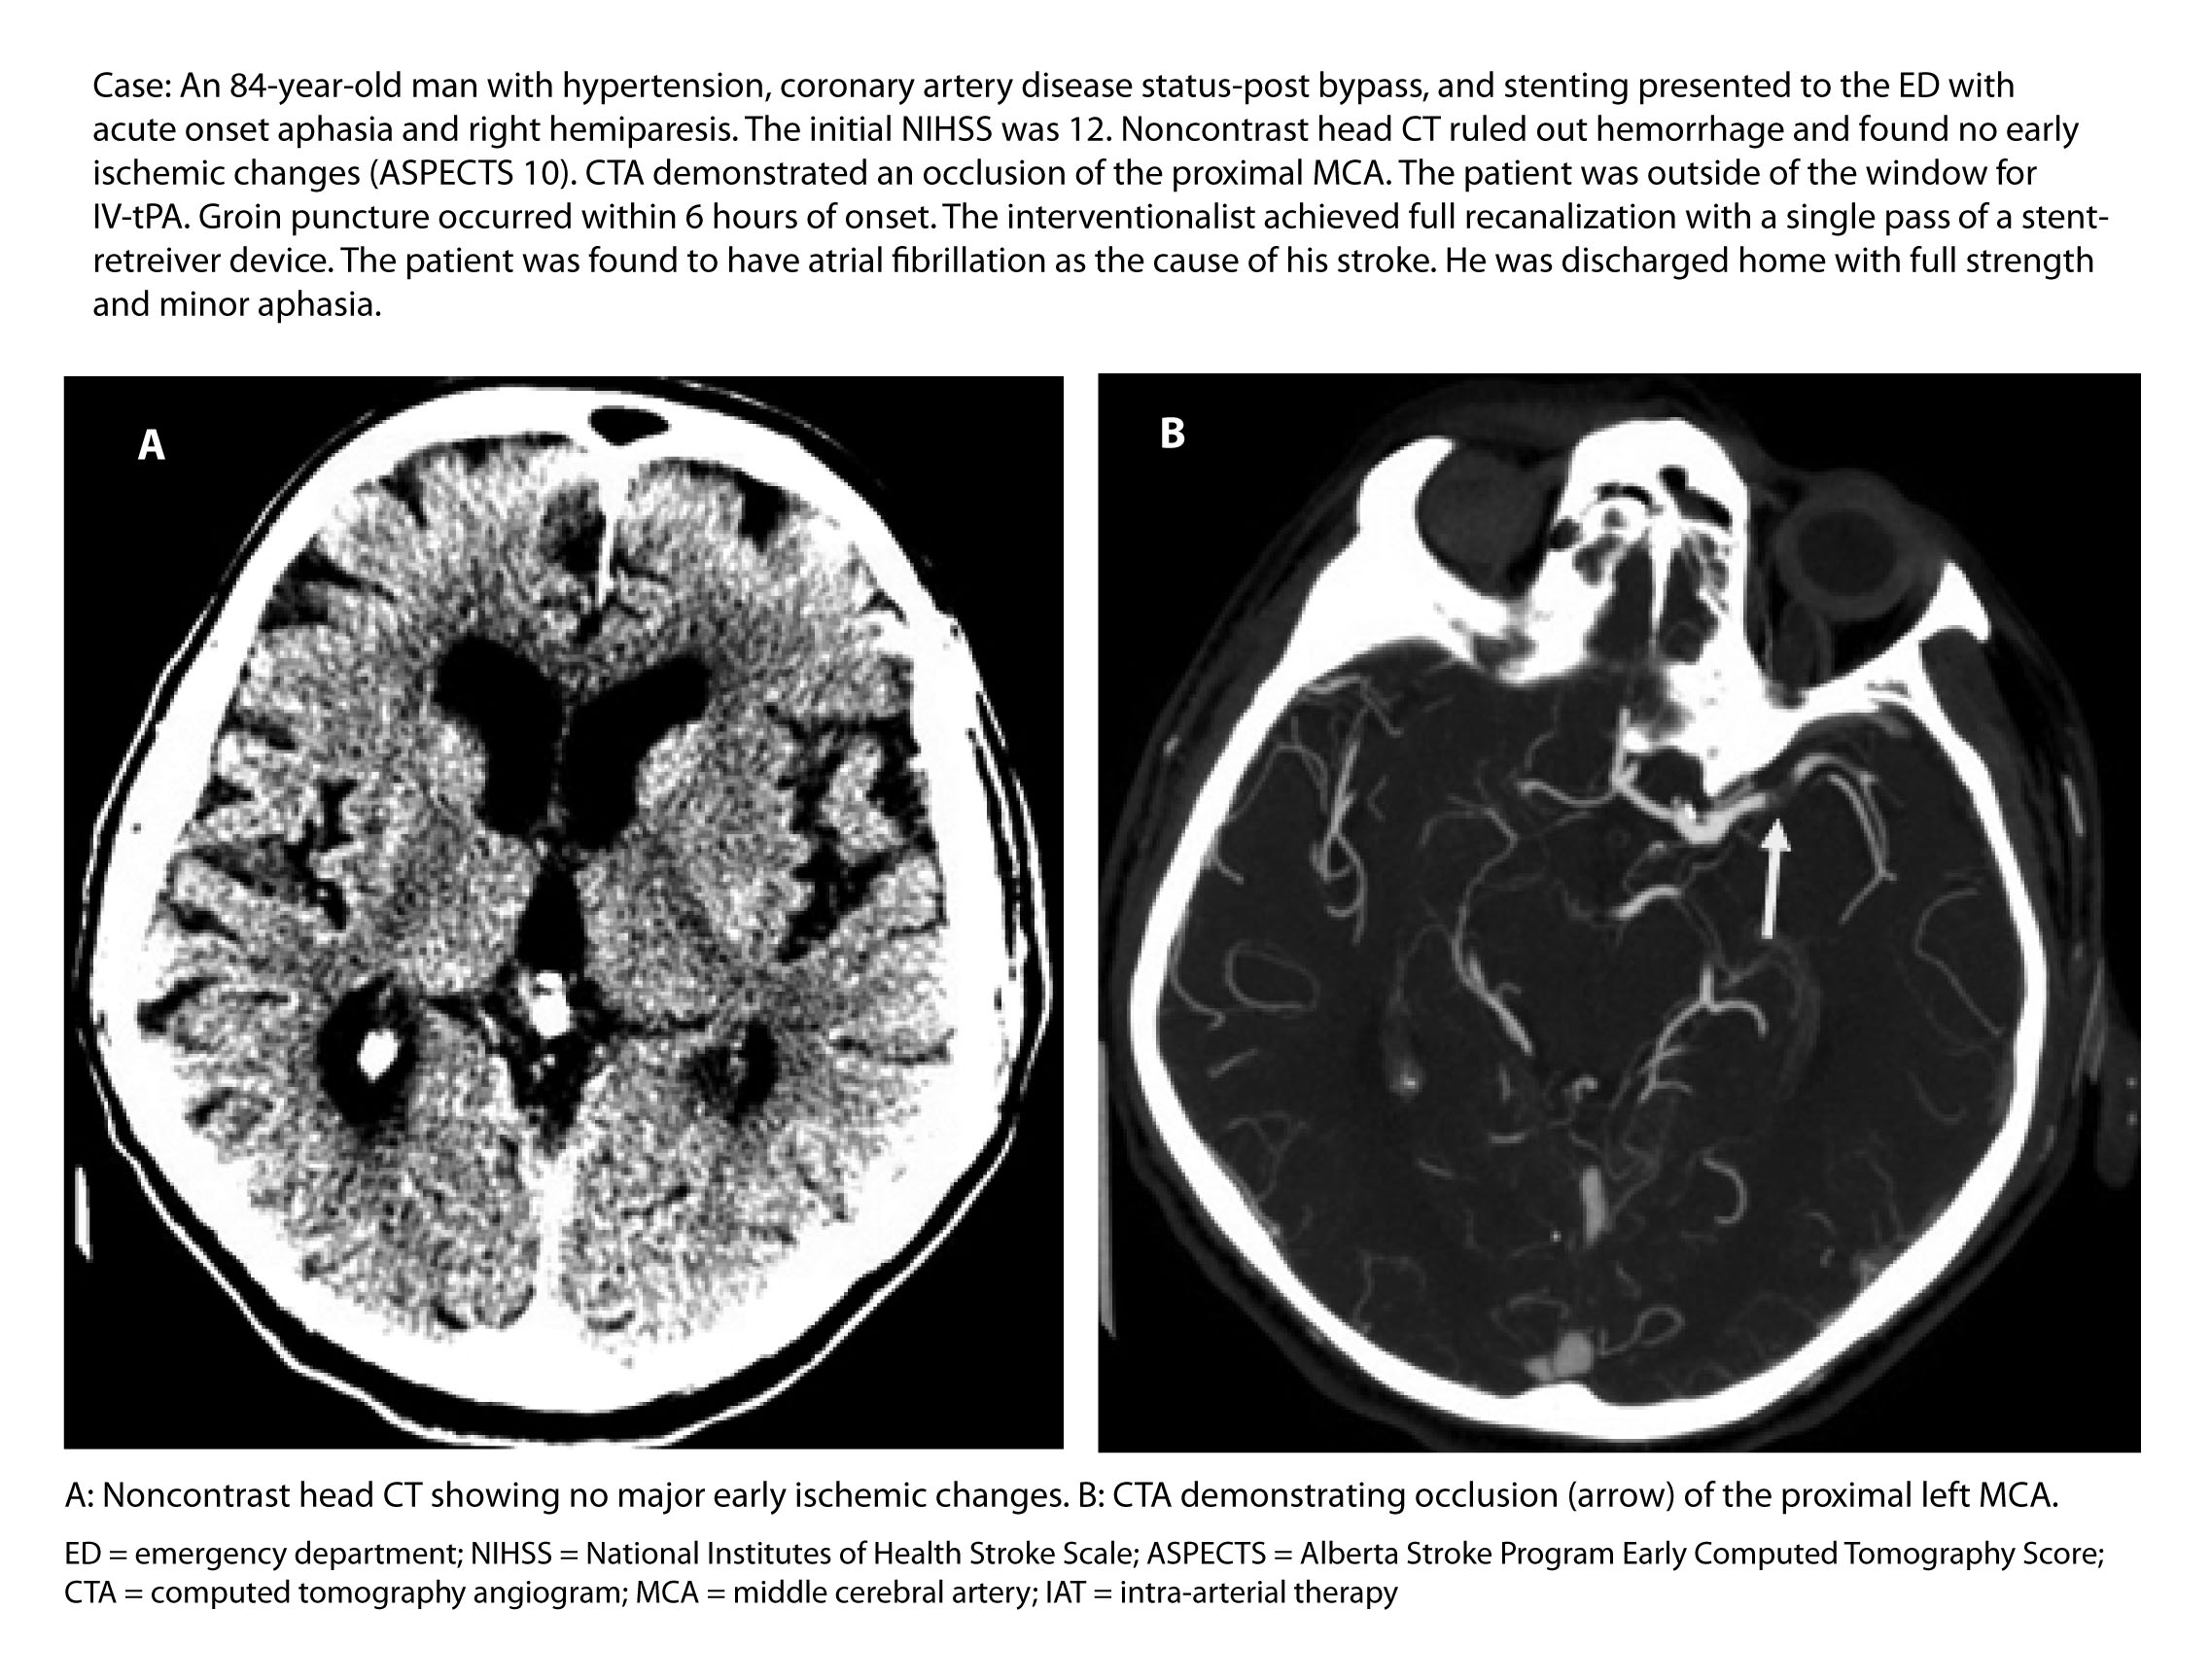

Diagnostic Workup of a Suspected LVO and IV-tPA as Bridging Therapy. The initial diagnostic evaluation of patients being considered for IAT should be similar to that performed on any stroke patient being considered for IV thrombolysis. (See Table 1 and Figure 1.) In fact, the vast majority of patients included in recent endovascular trials received IV-tPA in addition to intra-arterial treatment. The number of patients who first underwent IV thrombolysis prior to IAT ranged from 73-100% in these trials.45,47 IV-tPA remains an important method of therapy for patients with LVO for two reasons, ultimately demonstrating the significance of concurrent IV alteplase administration in eligible patients, even if they are planned for subsequent IAT.

Figure 1. Suggested Diagnostic and Treatment Algorithm for Patients with Acute Ischemic Stroke Due to a Large Vessel Occlusion

Once the decision to administer tPA is made, the patient next should undergo emergent noninvasive angiography to confirm the presence of an LVO, if suspected. (See Figure 1.) A high-quality CT angiogram (CTA) of the head and neck will provide data on the location of an intracranial LVO, the quality of collateralization, as well as the presence of comorbid extracranial carotid stenosis that may require concurrent intervention. Endovascular trials that did not require the confirmation of an LVO by CTA prior to randomization failed to demonstrate any benefit of endovascular treatment.54-56 If an acute occlusion of a proximal intracranial artery, such as the MCA or ICA, is discovered on angiography, then the patient may be a candidate for mechanical thrombectomy if there remains a large mismatch between ischemic penumbra (i.e., tissue at risk) and core infarct (i.e., established stroke). However, if there is a large area of established infarct, the patient is unlikely to benefit from intra-arterial intervention.52 The presence of core infarct can be determined through multiple techniques and has been used successfully to select patients for endovascular therapy through such modalities as noncontrast cranial CT,6,44 collateral scores on CTA,44,57 CT perfusion scans,45,46 and MRI.47,58 Often, the Alberta Stroke Program Early Computed Tomography Score (ASPECTS) is used to standardly quantify the amount of early ischemic changes in the MCA territory present on a noncontrast head CT.59 The ASPECTS scale is a 10-point, validated scoring system, where an initial score of 10 indicates a normal CT scan, and 1 point is subtracted for each abnormal area within 10 pre-specified regions of the cortex and deep subcortical structures. The higher the ASPECTS number, the smaller the core infarct, the larger the presumed ischemic penumbra, and the better the patient is a candidate for intervention. Many of the recent endovascular trials used a cutoff of 6 or better on the ASPECTS scale as part of the inclusionary criteria for trial selection, as these patients are thought to have the largest areas of salvageable brain tissue.44,46,47

Figure 2a. Neurovascular Imaging for an Acute Ischemic Stroke Patient Undergoing Evaluation for Endovascular Intervention |

|

Figure 2b. Neurovascular Imaging for an Acute Ischemic Stroke Patient Undergoing Evaluation for Endovascular Intervention |

![]() |